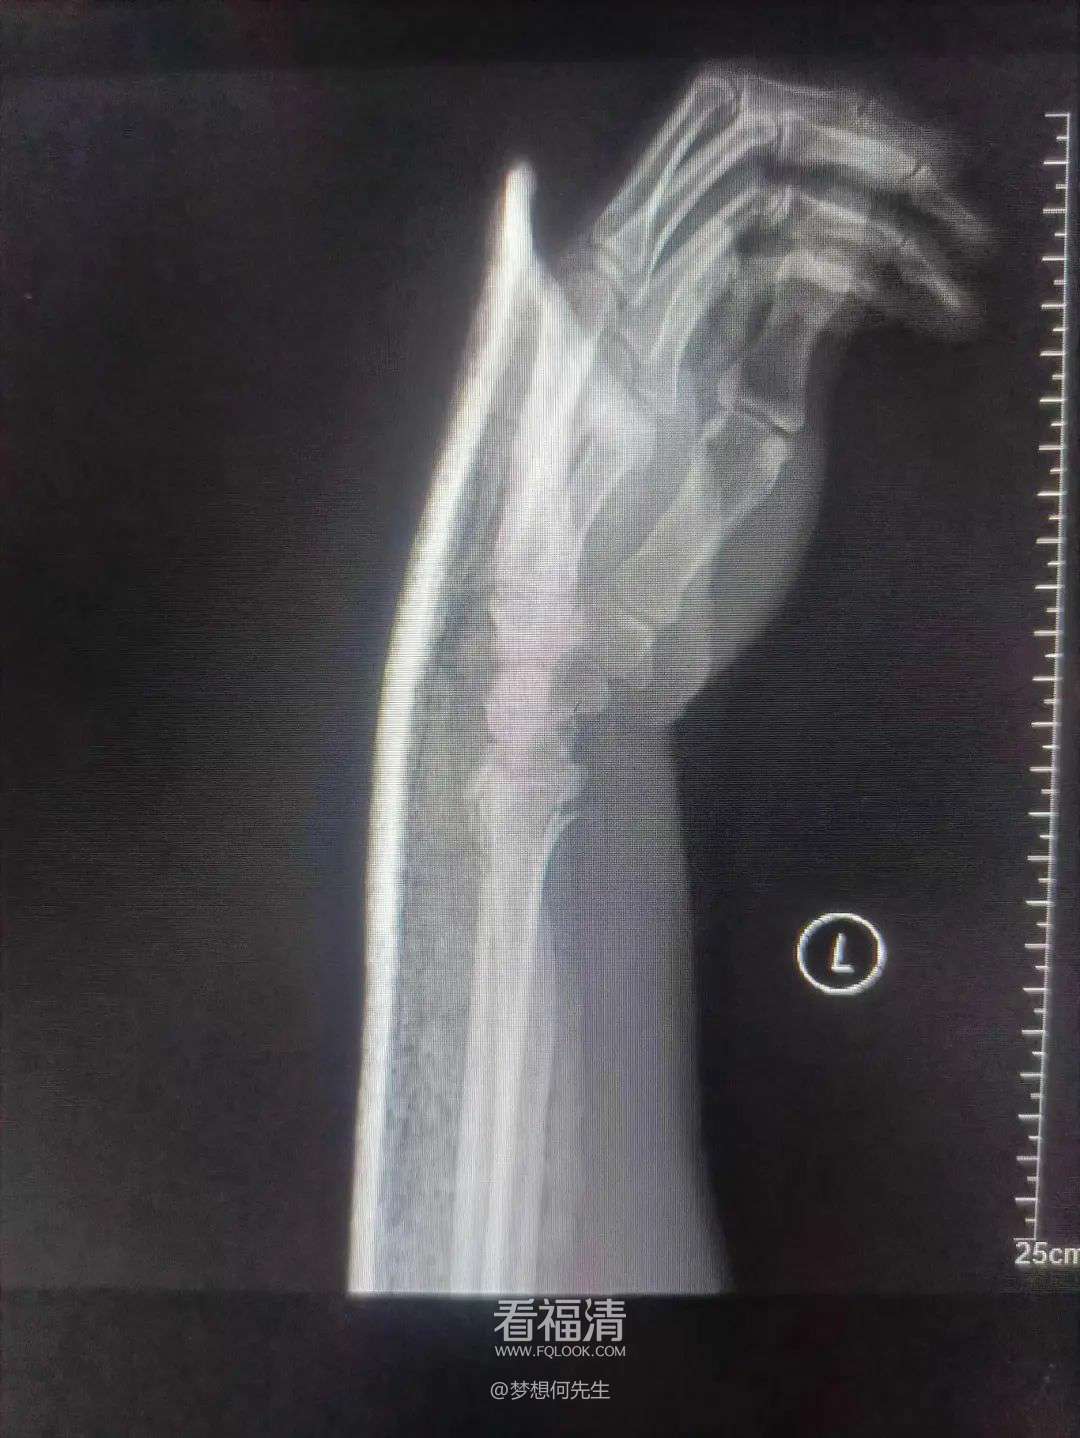

患者39岁,因外伤导致左手疼痛难忍,前来福清市第五医院中医骨科门诊寻求治疗。经过详细检查,患者被确诊为左侧桡骨远端粉碎性骨折伴下尺桡关节脱位。接诊的王征勇运用精湛的正骨手法进行复位,并在中医正骨理论的指导下,使用石膏进行固定。这种治疗方案有效地稳定了复位后的桡骨远端骨折,促进了骨折的愈合,避免了不必要的手术治疗,同时显著减轻了患者的疼痛感。

复位前

复位后